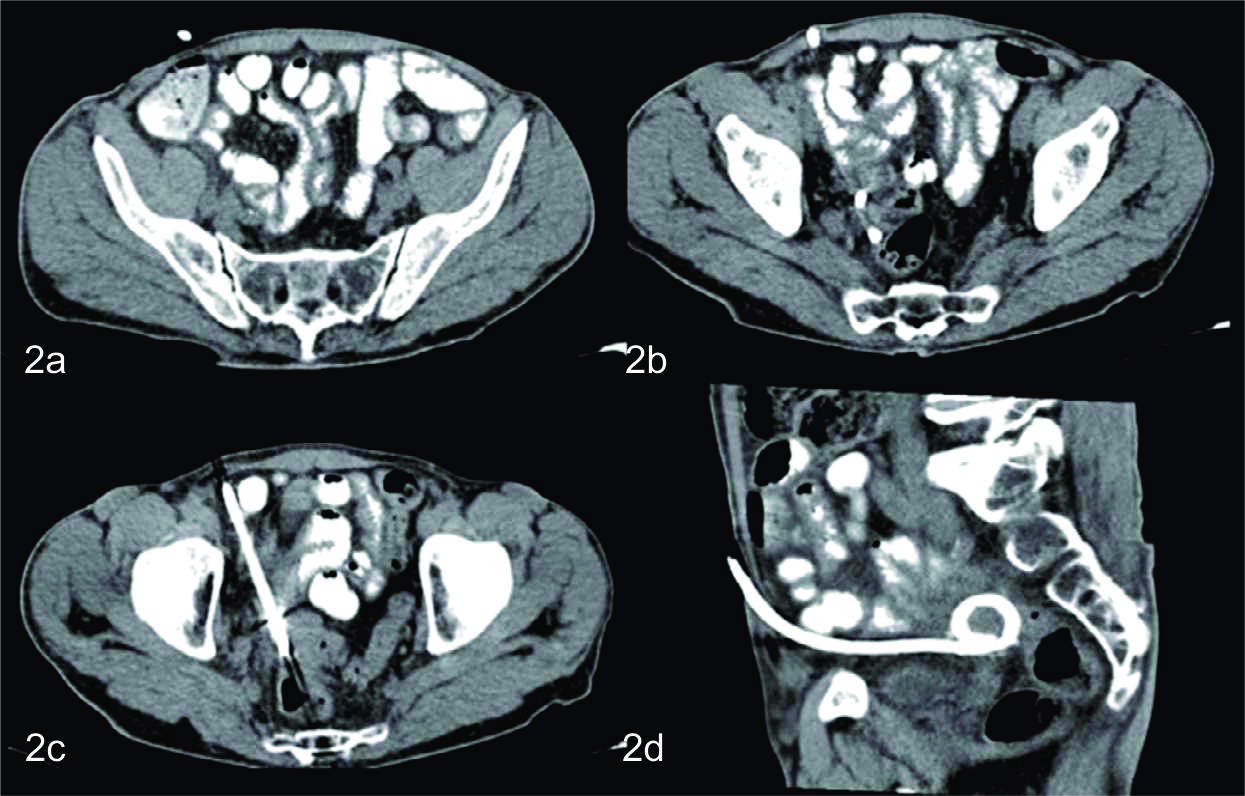

Se le realizo TC con Medio de contraste intravenoso (MC i/v) en fase portal , apreciándose asas intestinales distendidas, algunas de ellas con niveles hidro-aereos en su interior. Se observa además a nivel de la pelvis, con epicentro en el fondo de saco de Douglas una colección redondeada, bien definida, de paredes finas y regulares con contenido hipodenso.

La misma, por su sector superior derecho se extendía hasta la fosa iliaca reconociéndose a dicho nivel tres pequeñas imágenes calcicas redondeadas, que fueron interpretadas como apendicolitos, elemento semiológico fundamental, para arribar al diagnóstico de apendicitis aguda complicada con absceso pelviano. Con dicho planteo diagnostico se discute junto con los cirujanos de guardia tratantes la posibilidad de realizar manejo percutáneo del absceso como tratamiento inicial, y determinan en la evolución la eventualidad de realizar cirugía definitiva. El procedimiento fue realizado bajo guía tomográfica con el paciente en decúbito supino, Se valoro ventana de acceso y se procedió a topografiar el sitio de abordaje en piel, que fue a nivel de hipogastrio. Se procedió a colocar el drenaje bajo técnica de Trocar, utilizándose un drenaje multipropósito 14 F. El mismo se dejó abierto a bolsa colectora con llave de tres vías. El material obtenido fue francamente purulento y se tomaron muestras del mismo para análisis bacteriológico, cultivando flora polimicrobiana.

En el control tomográfico posterior, realizado a los 7 días del procedimiento, se reconoce el catéter de drenaje ingresando por la pared anterior del abdomen, el cual se dirige caudomedial con su extremo en el fondo de saco de Douglas, sin evidencia de colección residual. Se decide realizar prueba terapéutica cerrando el drenaje. Dada la buena evolución, el mismo es retirado a las 48 hs.